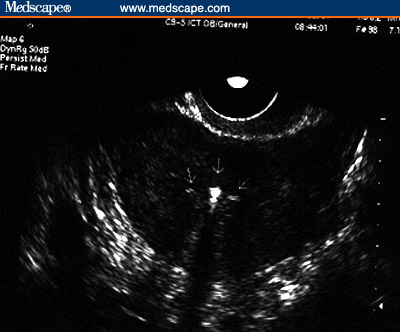

Figure 1. Sonographic appearance of the LNG-IUS. Sagittal view of the

uterus: the proximal and distal ends of the vertical arm of the device, in

the internal cervical os and the fundal region, respectively (arrows).